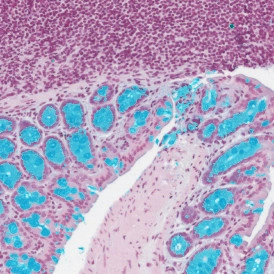

The IHC Meta Cells App combines the detection of IHC/HC stained metastructures (e.g., Langerhans islets, Tumor - Stroma) with single-cell detection (segmentation of cells into nucleus, perinuclear area, and/or cytoplasm). Detected cells can be classified and visualized as being within or outside detected metastructures. Each detected area and cell compartment is measured for up to 20 intensity, statistic, and morphometric parameters.

The IHC Small Intestine - Dots App provides nuclei segmentation and detection of tissue and villi based on nuclei staining (crypts need to be defined manually). Furthermore, it allows dot detection for one dot markers (CISH, RNAScope, SISH) within villi and crypt areas. Dot parameters are provided for villi and crypts and for dots and include count, mean intensity, total dot area, the sum of intensity.

The Mucin Swiss Roll App allows for detection of the swiss roll, and the segmentation into different subclasses (mucosa, immune cell follicles, connective tissue, background). Further it detects nuclei and (e.g. PAS stained) mucin. The App outputs area (µm2) of detected tissues/tissue classes, count of total cells and in each detected area as well as the area of stained mucin in the entire tissue and within the subclasses..

The IHC Swiss Roll App allows for detection of the swiss roll, and the segmentation into different subclasses (mucosa, immune cell follicles, connective tissue, background). Further it detects nuclei and identifies phenotypes based on specific stains. The App outputs area (µm2) of detected tissues/tissue classes, count of total cells as well as in each detected area. Count and % of specific phenotype detected in total as well as in the tissue classes.

The IF Swiss Roll App allows for detection of the swiss roll, and the segmentation into different subclasses (mucosa, immune cell follicles, connective tissue, background). Further it detects nuclei and identifies phenotypes based on specific IF stains. The App outputs area (µm2) of detected tissues/tissue classes, count of total cells as well as in each detected area. Count and % of specific phenotype detected in total as well as in the tissue classes.